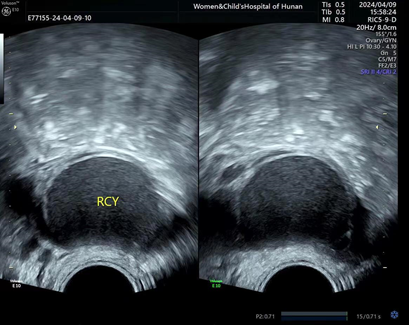

1、卵巢子宫内膜异位囊肿的典型超声特征为:囊内容物呈“磨玻璃样”回声 , 囊壁较厚 。

彩色多普勒血流显示 , 囊肿内部无血流信号 , 仅在囊壁或分隔上见条状血流信号 。

多数病灶呈单房 , 少数呈多房或多发囊肿 。

4、卵巢子宫内膜异位囊肿常与子宫盆壁粘连、固定 。